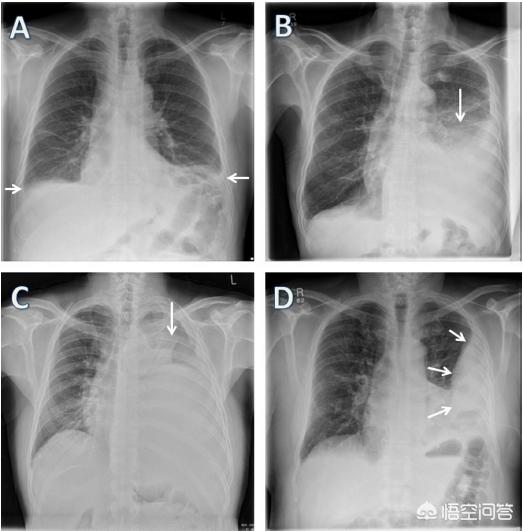

正常的情况下,在双肺和胸壁之间形成胸膜腔里有一层很薄很薄的液体,像润滑油一样,主要是起润滑的作用,这层胸腔积液伴随呼吸周期和胸腔压力能够保持吸收和滤出动态平稳,不至于造成胸水集聚。但是异常的情况下,任何原因造成胸水吸收过慢或者形成过快,势必导致胸腔积液增多,形成胸水。

胸水最严重的后果是导致患者出现呼吸费力或者气促,而且大部分胸腔积液患者伴发咳嗽和胸部疼痛。

导致胸水的原因有肺炎、肺结核、低蛋白血症、肝硬化、肾病综合征、心力衰竭、胸部损伤等。